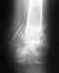

В дек 2009 г. операция по Уоткинсу-Каплану пластика ключично-клюв связки по поводу закрытого вывих акр конца ключицы.

С марта 2010 начал "активничать" ЛФК, "тянулся", но никаких силовых. В апреле на Rграмме перелом одной из двух спиц, с образованием подвывиха. Сейчас. Удалить метал и оставить все так. Поставить заново спицы. Поставить жесткую пластину, боюсь металлоза. Объем движений - жить можно, но хотелось бы больше. Уважаемые доктора, посоветуйте как быть?